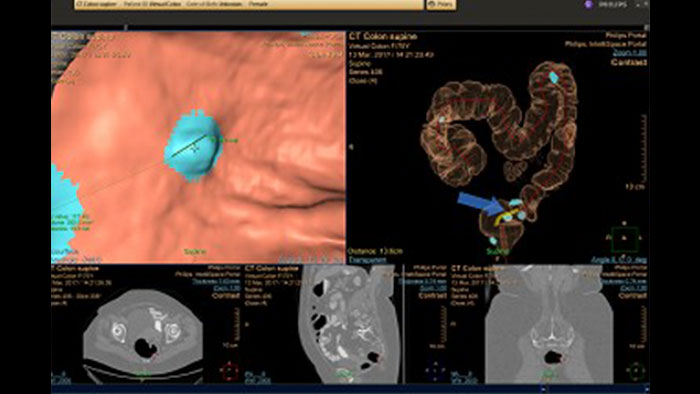

Reducing reading times in virtual colonoscopy

Philips exclusive CT Virtual Colonoscopy application enables 3D visualization of colon scans. The application automatically segments the air-filled colon and displays a calculated center line. The Perspective Filet view provides a synchronized display of the full colon surface wall with a single unidirectional view, reducing the need to review in both directions.

Benefits

- Colon editing GUI with improved workflow and usability. - Simplified floating dialog with editing tools per segment. - New centerline drawing capabilities. - VC user preference for: colon color, cleaning method, “Save User Settings”. - New “mirror layout” for dual monitor mode.